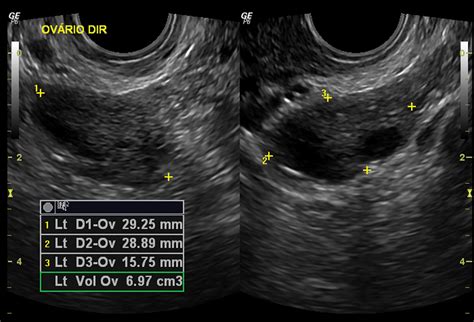

Ovary volume is typically measured using ultrasound imaging, a non-invasive procedure that uses sound waves to create images of the internal organs. The most common method for measuring ovary volume is through transvaginal ultrasound, which provides a clearer view of the pelvic organs. The volume is calculated using the formula for the volume of an ellipsoid:

📝 Note: The formula for calculating ovary volume is V = 0.523 × (length × width × height).

During an ultrasound, the technician will measure the length, width, and height of each ovary. These measurements are then plugged into the formula to determine the volume. The results are usually expressed in cubic centimeters (cm³).

Age Group Normal Ovary Volume (cm³)

Prepubertal (before menarche) 1-3 cm³

Reproductive years (18-45) 6-10 cm³

Perimenopausal (45-55) 4-8 cm³

Postmenopausal (55+) 2-5 cm³